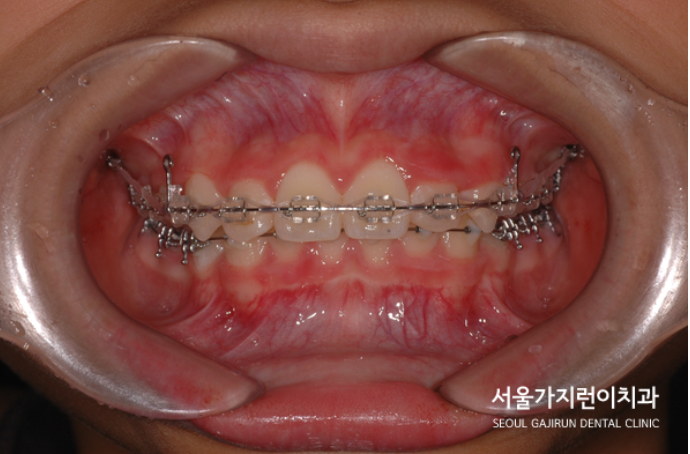

이후에는 돌출감을 해소하기 위한 미니스크류를 활용한 치아교정이 이루어졌는데요. (미니스크류는 잇몸에 박혀있는 작은 나사와 같은 장치를 말합니다. ) 미니스크류는 간단한 국소마취로도 식립이 가능하고 잇몸뼈에 직접 식립하기 때문에 강력한 고정힘으로 정밀하게 치아이동이 가능한데요. 치료를 하지 않았다면 치아의 배열이 심하게 비뚤어지고 상악 전치가 뻐드러졌을 것을 1차 성장교정(헤드기어)를 통해 만족할 수 있는 경과를 만들어냈습니다.